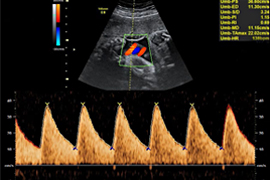

Dopplersonographie

Blutflussmessung

Bei der Dopplersonographie werden Blutgefäße dargestellt und die Strömungsgeschwindigkeit des Blutes gemessen. So können die zuführenden mütterlichen Gefäße (Gebärmutterarterien) und die kindlichen Gefäße (z.B. Nabelschnurarterien, Hirnarterien, Venen) untersucht werden. Hierdurch ist es einerseits möglich, eine Risikobewertung für eine Wachstumsstörung beim Kind oder für die Entwicklung mütterlicher schwangerschaftsbedingter Erkrankungen vorzunehmen. Andererseits kann das kindliche Wohlergehen bei Auffälligkeiten sehr zuverlässig bestätigt und überwacht werden.

Die Versorgung des Kindes mit Sauerstoff und Nährstoffen erfolgt über Blutgefäße der Gebärmutter. Diese führen zum Mutterkuchen (=Plazenta), der fest an der Gebärmutterhöhle anliegt. Über die Plazenta werden so die versorgenden Stoffe zur Nabelschnur und schließlich zum Kind transportiert. Wir können an bestimmten Blutgefäßen dieses kindlichen Kreislaufs (in Nabelschnur, Gehirn, Leber) prüfen, ob es dem Kind gut geht – beim Erwachsenen würden wir Blutdruck messen! Ebenso können die Blutgefäße, die zur Gebärmutter führen, überprüft werden.

Die Geschwindigkeit des Blutflusses und der Widerstand in den Blutgefäßen lassen sich in der Doppler-Ultraschalluntersuchung messen.